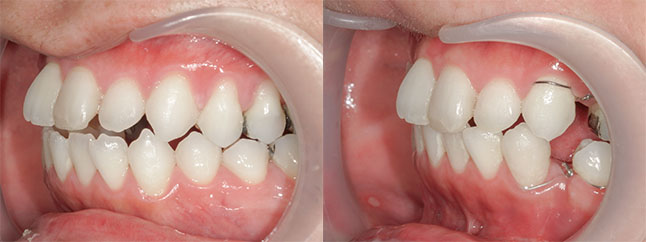

奈良県 20歳 女性

執刀医 辻和志

【治療内容】上下のアゴが前に出ていたため、上下のアゴの骨を切って後ろにさげました。

【費用】上下セットバック 2,307,800円(税込)

【リスク】全身麻酔で行うため全身の健康状態が悪い方は行うことができません。また、手術当日は安静にしていただく必要があります。